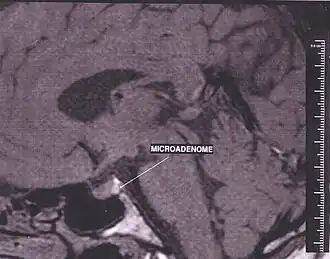

Een hypofysetumor is een (goed- of kwaadaardig) gezwel dat zich ontwikkelt in de hypofyse, een klein orgaantje dat onder de hersenen zit in een kleine benige ruimte, het Turkse zadel (sella turcica). Verreweg de meeste zijn goedaardig (in de zin van 'geen kanker') maar ze kunnen toch door verdringing van andere structuren ernstige klachten veroorzaken.